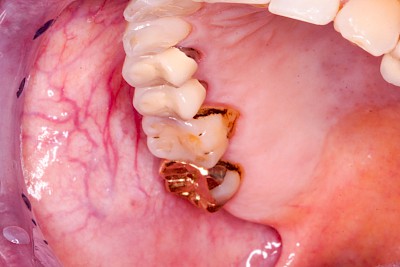

Einbiss & Bluterguss

Blutungen & Blutergüsse sind in den meisten Fälllen als ein Zeichen einer Verletzung wie z.B. einem Einbiss oder nach einem Sturz zu werten.

Wundheilungsstörungen

Nach operativen Eingriffen im Bereich der Mundhöhle (Zahn ziehen "Extraktion", Schleimhautprobenentnahmen "Biopsien" oder Tumoroperationen) kann es zu Wundheilungsstörungen mit Schwellungen, Rötungen und Nach-Blutungen, gestörter Sprache oder Kaufunktion kommen. Einzele Gesichtsbereiche können sich warm anfühlen und in seltenen Fällen kann es zu Fieber und reduziertem Allgemeinzustand kommen.

Wundheilungsstörungen24 Bilder